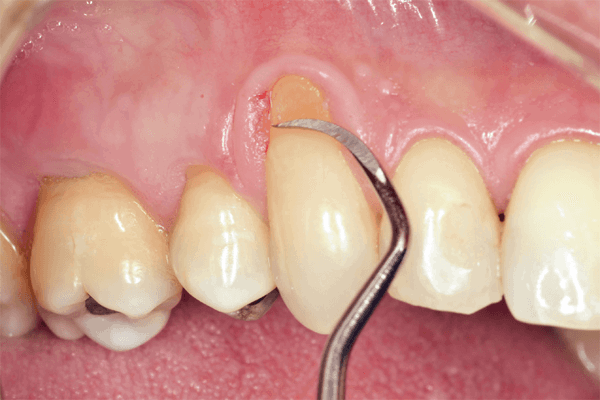

Recessão gengival é uma condição bastante comum entre pacientes de ambos os sexos e em diferentes idades, aumentando sua frequência com o passar dos anos. As maiores queixas dos pacientes com recessão gengival são hipersensibilidade radicular e aspecto antiestético.

Para isto, existem diversos tratamentos, sendo as cirurgias de enxerto para recobrimento radicular as mais utilizadas.

A cobertura total das raízes por tecidos gengivais espessos e saudáveis é indispensável para eliminar esses sintomas severos. No entanto, é de grande importância o conhecimento de suas técnicas, indicações e contraindicações, a partir das considerações anatômicas de cada caso.